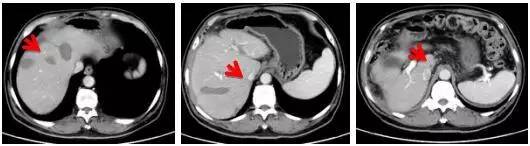

患者微波消融手术之后,病灶消融完全

消融前

消融后